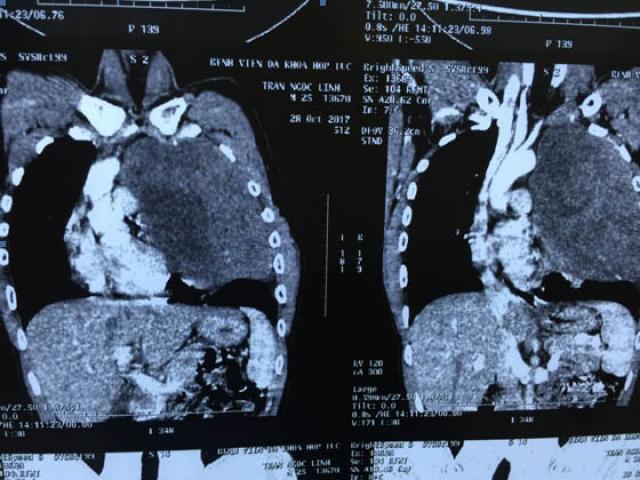

Một người đàn ông 32 tuổi đã phải chịu đựng những cơn đau ngực dai dẳng suốt 10 năm mà các bác sĩ không phát hiện...